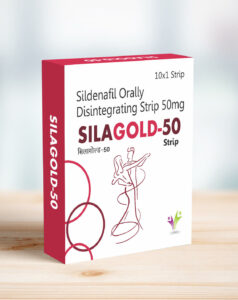

Medicinal or Drug Products

Strips Are Fortune Strips For The Patients Who Suffer From Erectile Dysfunction. These Strips Are A Perfect Re-Placement For Pills, Jelly And Chewable. By Unique Formulations The Active Ingredient Sildenafil Citrate Is Absorbed Via The Oral Mucosa And Directly Enters The Systemic Circulation Which Works Faster When Compared To Other Dosage Forms When Absorbed Through The Stomach.

Medicinal or Drug Products

Strips Are Fortune Strips For The Patients Who Suffer From Erectile Dysfunction. These Strips Are A Perfect Re-Placement For Pills, Jelly And Chewable. By Unique Formulations The Active Ingredient Sildenafil Citrate Is Absorbed Via The Oral Mucosa And Directly Enters The Systemic Circulation Which Works Faster When Compared To Other Dosage Forms When Absorbed Through The Stomach.

Silagold 50 Oral Thin Film represents this advanced technology, offering swift absorption into the bloodstream for immediate results. With no water required, it’s perfect for active, on-the-go lifestyles. The films dissolve effortlessly in the mouth, eliminating the risk of choking and making medication administration hassle-free.

Lightweight, compact, and easy to carry, oral thin films cater to all age groups. They ensure enhanced bioavailability, precise dosing, and a pleasant experience compared to traditional tablets or capsules. Step into the future of medicine with Silagold 50 Oral Thin Film – redefining how you experience wellness.

Compact, lightweight, and easy to use, oral thin films are suitable for all age groups. With enhanced bioavailability and precise dosing, they deliver the perfect blend of functionality and comfort. Experience a modern approach to medication with Silagold 50 Oral Thin Film, your go-to solution for seamless drug delivery.